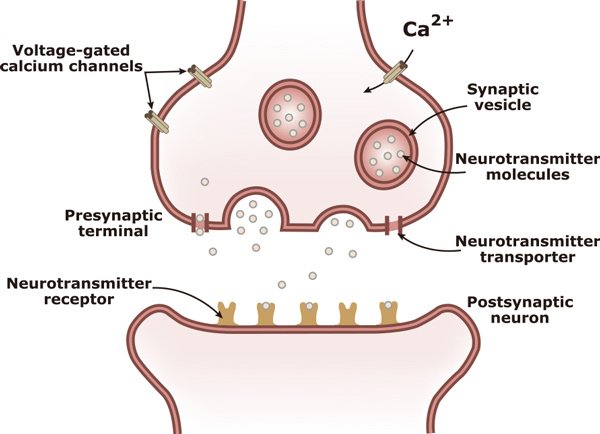

Neurotransmission is the process in which a neurochemical signal is transmitted from one neuron to an adjacent neuron. Neurotransmitters are released by the presynaptic neuron, travel across the synaptic cleft, and then bind to and activate receptors on the postsynaptic neuron. There are many different types of neurotransmitters, including acetylcholine, amino acids (asparagine, GABA, glutamate, and glycine), monoamines (dopamine, histamine, epinephrine, and norepinephrine), trace amines, purines and a variety of neuropeptides.